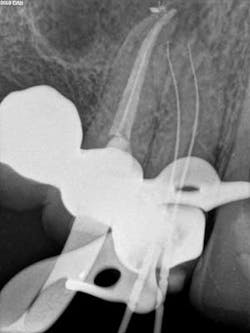

A 50-year-old male presented to my office on referral from his general dentist for evaluation of a large, periapical radiolucency relating to Nos. 4 and 5. Appropriate bitewing and peri-apical radiographs were taken (Fig. 1) for initial evaluation. After all clinical testing was performed, the recommendation was made to take a narrow-field CBCT image of teeth Nos. 4 and 5 (Figs. 2 and 3). The axial view reveals an untreated buccal canal on tooth No. 4 and potential separated instruments in both the buccal and palatal canal space of No. 5. Tooth No. 5 (Fig. 3) shows a short fill, meaning the entire canal space may not have been properly shaped and cleaned. With the three-dimensional images, we now have a better understanding of why these teeth present with post-treatment disease. This information is extremely important when discussing etiology and prognosis with our patients. It will also financially benefit the patient to maintain his existing fixed prosthesis with conservative retreatment of Nos. 4 and 5, knowing that we should have a high degree of long-term success seeing a clear etiology of the post-treatment disease.

The patient was appointed to start NSRCT retreatment on tooth Nos. 4 and 5. Upon the initial visit after proper anesthesia and rubber dam isolation, the teeth were treated using a surgical operating microscope. Conservative access was gained through the occlusal of No. 4, the untreated buccal canal was located and treated, and the palatal canal presented with a gutta percha fill. The palatal canal was retreated and both canals where packed with Ca(OH)2 paste for 10 days. At the patient’s next visit, No. 4 remained asymptomatic. After proper irrigation and additional cleaning and shaping, No. 4 was obturated and a coronal seal placed at this appointment. Endodontic therapy is not complete until we have coronally sealed the tooth. Tooth No. 5 was accessed after the obturation of No. 4, and it was noted that the metallic-like images we had noted on the CBCT scan were indeed Thermafil metal carriers. Each carrier was isolated under the microsope and removed in a similar fashion to the removal of a separated instrument (Fig. 4). After proper cleaning and shaping, No. 5 was packed with an interappointment Ca(OH)2 dressing, and the patient was appointed for completion of No. 5.